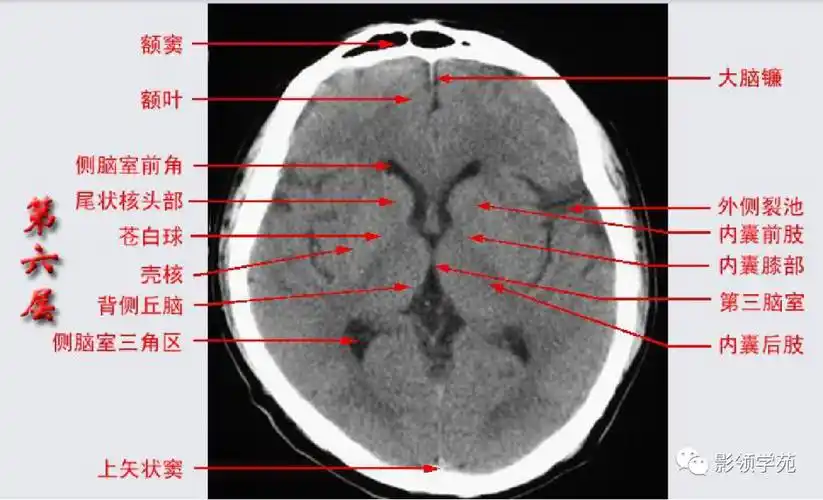

影像医生必须掌握的头颅ct解剖与常见出血梗死判读

头颅ct 解剖图谱,人手一份

头颅ct断层解剖